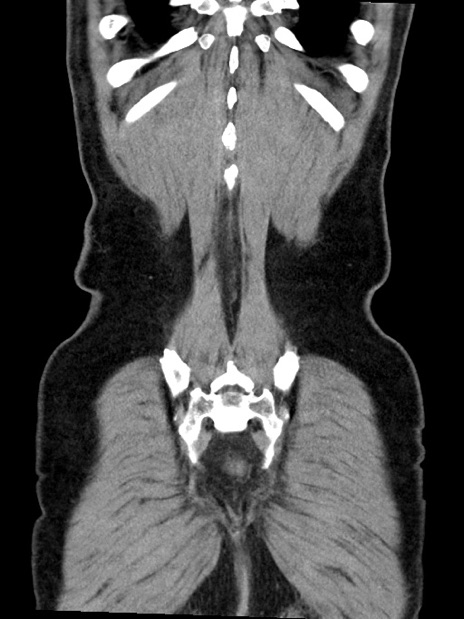

症例35(冠状断像)

【症例】70歳代 男性

【主訴】腹部膨満、嘔吐

【現病歴】昨日より腹部膨満感出現。本日増悪し、仙痛出現。嘔吐あり、受診。

【既往歴】糖尿病、胆摘後

【身体所見】BP 149/80mmHg、HR 74/min、BT 35.9℃、腹部:膨満、軟、圧痛なし。腸雑音減弱あり。上腹部正中切開瘢痕あり。

【データ】WBC 13500、CRP 1.72